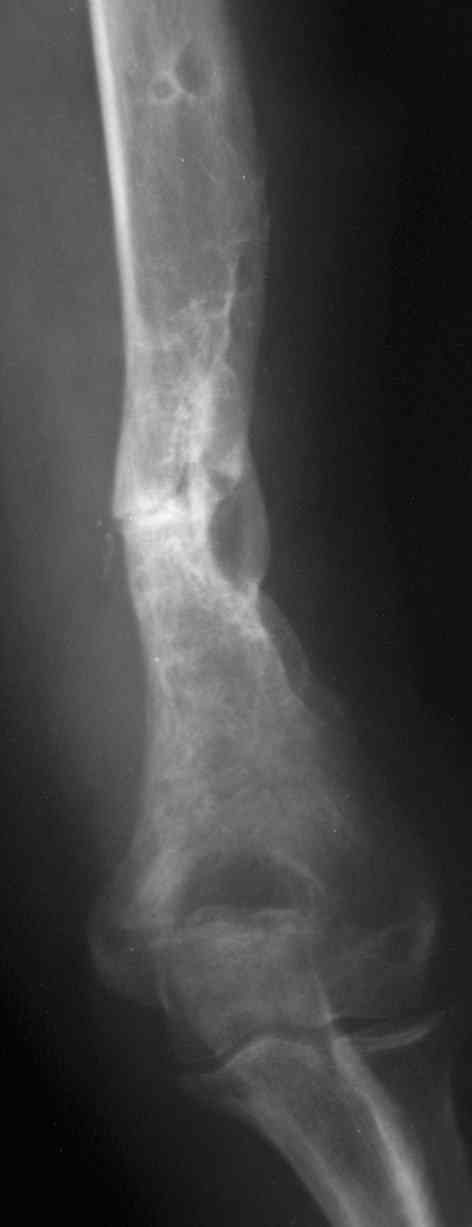

Лечение вторичного ложного сустава плеча особенно в дистальных отделах очень трудная задача. Результат несостоятельного остеосинтеза, приведший к ложному суставу осложнен коротким дистальным склеризированным участком и полным отслоением от мягких ткани в дистальном отделе плеча.

Проведение интрамедуллярного гвоздя в дистальный отдел плеча технически несложно, но с дополнительной травматизацией, и один дистальный винт не создаст стабильность.

Без открытия фокуса не обойтись. Насчет декортикации - кто-то уже пытался создать декортикацию. На "вторичном" ложном суставе обычно вместо кортекса с мягкими тканями, особенно в этом случае, огромная псевдосуставная полость.

В зоне патологии нарушено кровообращение, поэтому

трудно предположить, какое из главное - внутрикостное или периостальное.

Мне кажется, главным является создание стабильности между проксимальным и дистальным отделами плеча.

В подготовке места для укладки костной пластики можно идти на небольшое укорочение до образования "pepper sign" т.е. образования "росы".

У взрослых для плеча до 3 см укорочение и варус до 20 градусов и ротация до 10 градусов считаются

приемлемым.